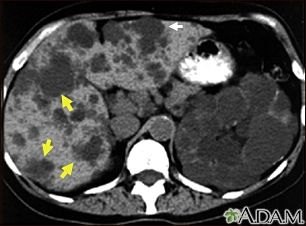

Kidney and liver cysts - CT scan